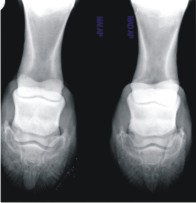

Metabolic bone diseases.